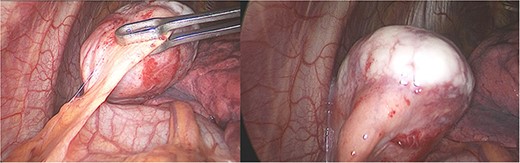

With these results, many diagnoses were among the differential, including pericardial cysts, oncogenic cysts, lymphoma, mesotelioma, metastasic tumors, sarcoma and other mediastinal tumors such as thymoma or teratoma. Therefore, surgical resection was decided through a thoracoscopic approach. A 40 × 30 × 30 mm pearly white, pedunculated and firmly encapsulated tumor was encountered at thoracoscopy. It was near the pericardium and in close contact with the left phrenic nerve. During dissection, it was impossible to retract the phrenic nerve completely; therefore, to avoid the risk of injury, a left posterolateral thoracotomy was performed. Afterward, the entirety of the mass was removed. We dissected it from surrounding structures and completely removed it along with a small portion of the pericardium to which it was attached. The rest of the procedure was completed without complications; a bovine pericardium patch was used to repair the pericardium defect, and finally, a 28 Fr. chest drain was placed (Fig. 2).

Laparoscopy, (a) hard white irregular tumor depends on the pericardium without invasion of the left phrenic nerve. (b) The tumor is adjacent to the lung but not invading it.